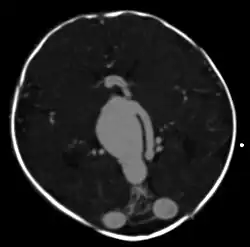

Axial image from computerized tomography angiogram showing arteriovenous communication in

vein of Galen malformation